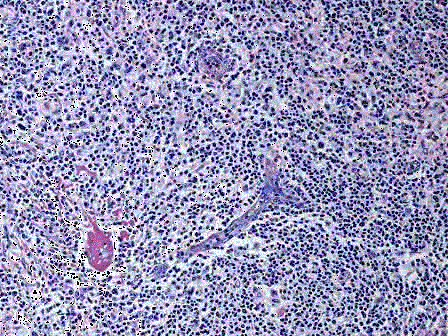

一患者颈部淋巴结肿大,直径达3cm,活检如图所示,淋巴滤泡弥漫增生,滤泡间小动脉增生、透明变性,并长入滤泡中心内;生发中心内小动脉内皮细胞肿胀,管壁内均质...

问题 一患者颈部淋巴结肿大,直径达3cm,活检如图所示,淋巴滤泡弥漫增生,滤泡间小动脉增生、透明变性,并长入滤泡中心内;生发中心内小动脉内皮细胞肿胀,管壁内均质、红染物质呈同心圆状沉积。应首先考虑何种疾病 ( )

选项 A.反应性滤泡增生 B.滤泡性淋巴瘤 C.巨大淋巴结增生症 D.套细胞淋巴瘤 E.胸腺瘤

答案 C